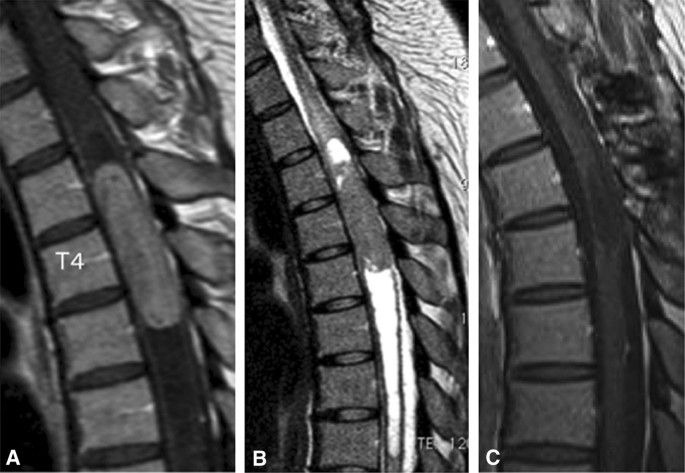

Inoue et al. [13] described a 25-year-old woman who presented with a 3-month history of back pain and difficulty walking (McCormick grade III). Magnetic resonance imaging revealed a homogeneously enhancing intramedullary T3-5 tumor with central canal expansion observed from T6 to T8 (Fig. 2). After a discussion of the risks and benefits of surgical intervention, the decision was made to perform surgical resection of the lesion. 5-ALA was administered 2 h prior to induction, and the tumor was exposed through a standard, posterior midline approach. Excitation light demonstrated vivid, heterogenous red fluorescence of the tumor (Fig. 3). The tumor was resected; although the tumor appeared to be contiguous with the cyst wall at the cranial, caudal, and ventral aspects of the cyst wall however no fluorescence was identified and this tissue was not resected (Fig. 3). Histopathological analysis of fluorescence-positive tissue demonstrated ependymoma (WHO grade II) (Fig. 3). Samples from the cranial and caudal end of the resection bed, which were fluorescence-negative, were negative for tumor cells. Post-operative magnetic resonance imaging confirmed complete resection, the patient demonstrated improvement in her neurologic status, and there was no evidence of recurrence at 24.1 months postoperatively. This case highlights the utility of 5-ALA fluorescence in guiding tumor resection and reducing unnecessary resection of normal tissue which could lead to neurologic deficit [13].

Magnetic resonance imaging (MRI) of the case described by Inoue et al. Preoperative T1-weighted (a) and T2 weighted (b) sagittal MRI revealed a homogeneously enhanced intramedullary T3-5 tumor with cyst formation extending to T8. Postoperative T1-weighted sagittal MRI (c) confirmed complete tumor resection with no signs of recurrence 2 years after surgery. Reprinted from Inoue et al. [13] 5-aminolevulinic acid fluorescence-guided resection of intramedullary ependymoma: Report of 9 cases. Neurosurgery 72:159–168. Reprinted with permission Oxford University Press